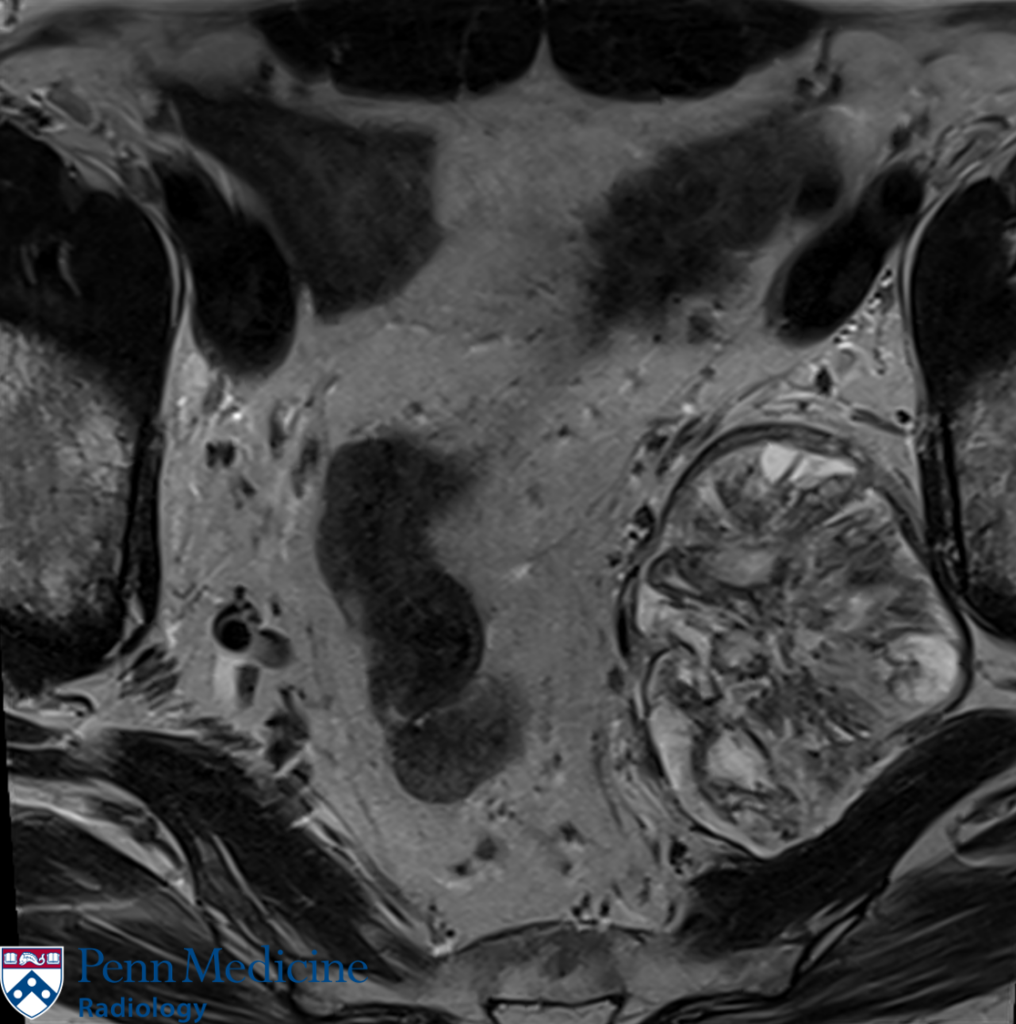

64-year-old man with prostate cancer

A 64-year-old man with prior prostate cancer.